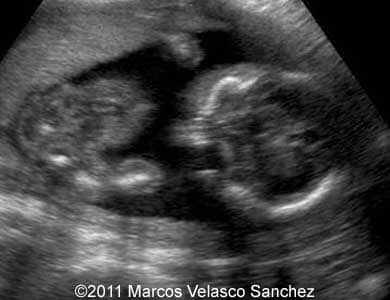

This is a case of a bilateral cleft lip associated with the cleft palate. A 25-year-old G2 P1 was referred to our department at 21 weeks of gestations. She had non-contributive personal or family history. We discovered bilateral cleft lip and palate. There were no other associated malformations.

Images 1- 4: Image 1; 21 weeks, Images 2-4; 24 weeks. Bilateral cleft lip and palate.